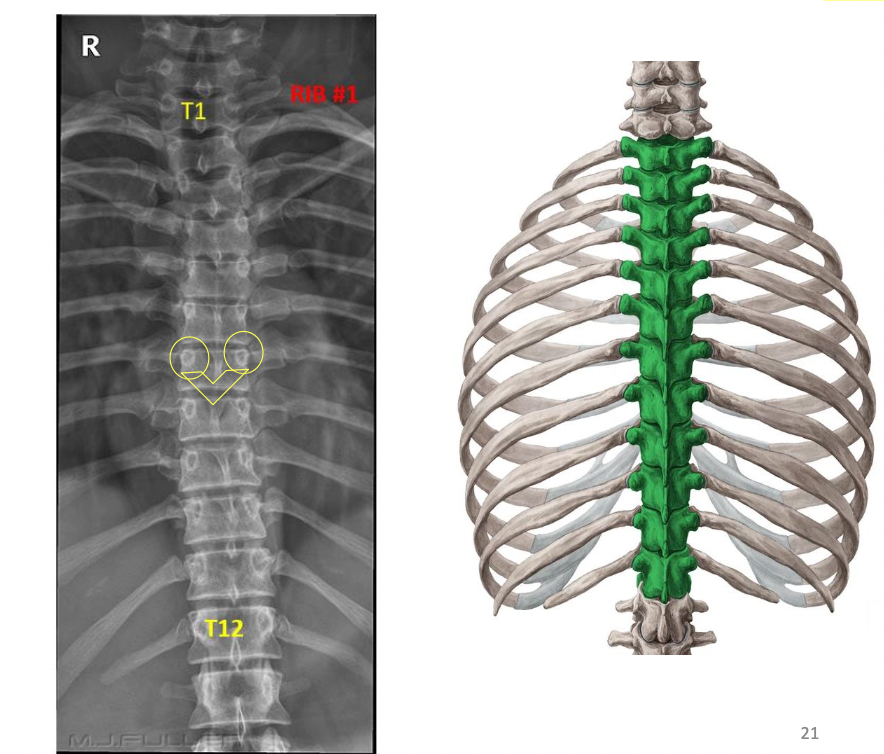

17

Q

Imaging of Thoracic Vertebrae

A

Look for 1st rib

Count vertebral bodies inferiorly from it

Examine disc spaces

Pedicles

Spinous processes

Look for abnormal curvatures

Look at rib attachments (ribs w/ transverse processes)